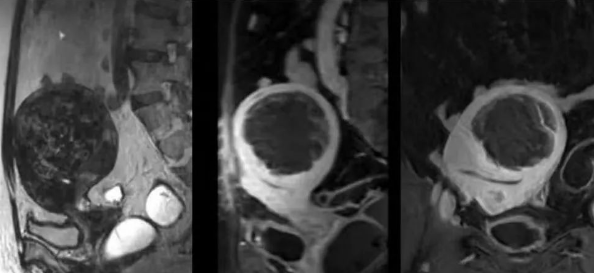

陳寶瑩主任首先給祝女士進(jìn)行了詳細(xì)的盆腔磁共振評(píng)估,發(fā)現(xiàn)子宮肌瘤比較大,直徑七公分,類(lèi)型和位置都適合做磁波刀治療。陳寶瑩主任立即為她制定了個(gè)性化治療方案,并為她完成幾項(xiàng)術(shù)前檢查。

治療當(dāng)天,為緩解祝女士的緊張心情,陳寶瑩主任和她進(jìn)行了充分溝通。術(shù)前準(zhǔn)備就緒后,治療正式開(kāi)始了。治療過(guò)程中,患者全程清醒,可以及時(shí)反饋治療感受。醫(yī)生也即時(shí)調(diào)整,確保整個(gè)治療安全有效,兩小時(shí)后治療順利結(jié)束,患者體驗(yàn)度好。即時(shí)評(píng)估發(fā)現(xiàn)7公分的子宮肌瘤被消融掉80%,達(dá)到了預(yù)期目標(biāo)。祝女士觀(guān)察一個(gè)小時(shí)后,沒(méi)有什么不舒服即回家了。